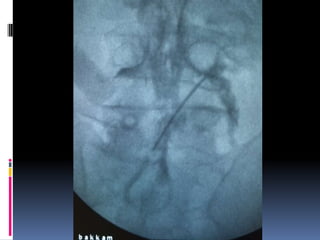

Epidural analgesia(failures)

Epidural analgesia

(failures)

Epidural failures (guess?)

Epidural failures

 Loss of resistance

Catheter placement

 Cervical – 1cm

 Thoracic-1.5 cm

 Lumbar – 2 cm

 Dermatomal involvement

 Calculation